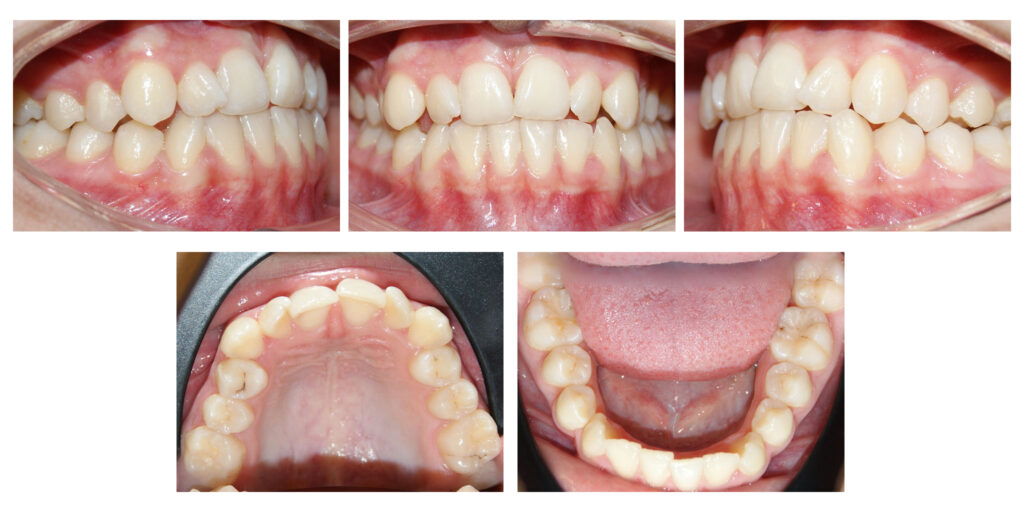

Pentru că detaliile fac diferența  – a se remarca înălțarea și lărgirea zâmbetului #contenție fixă